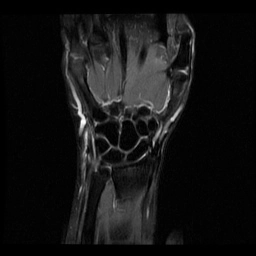

Đứt dây chằng thuyền-nguyệt (Scapholunate ligament tear)

16/03/2026